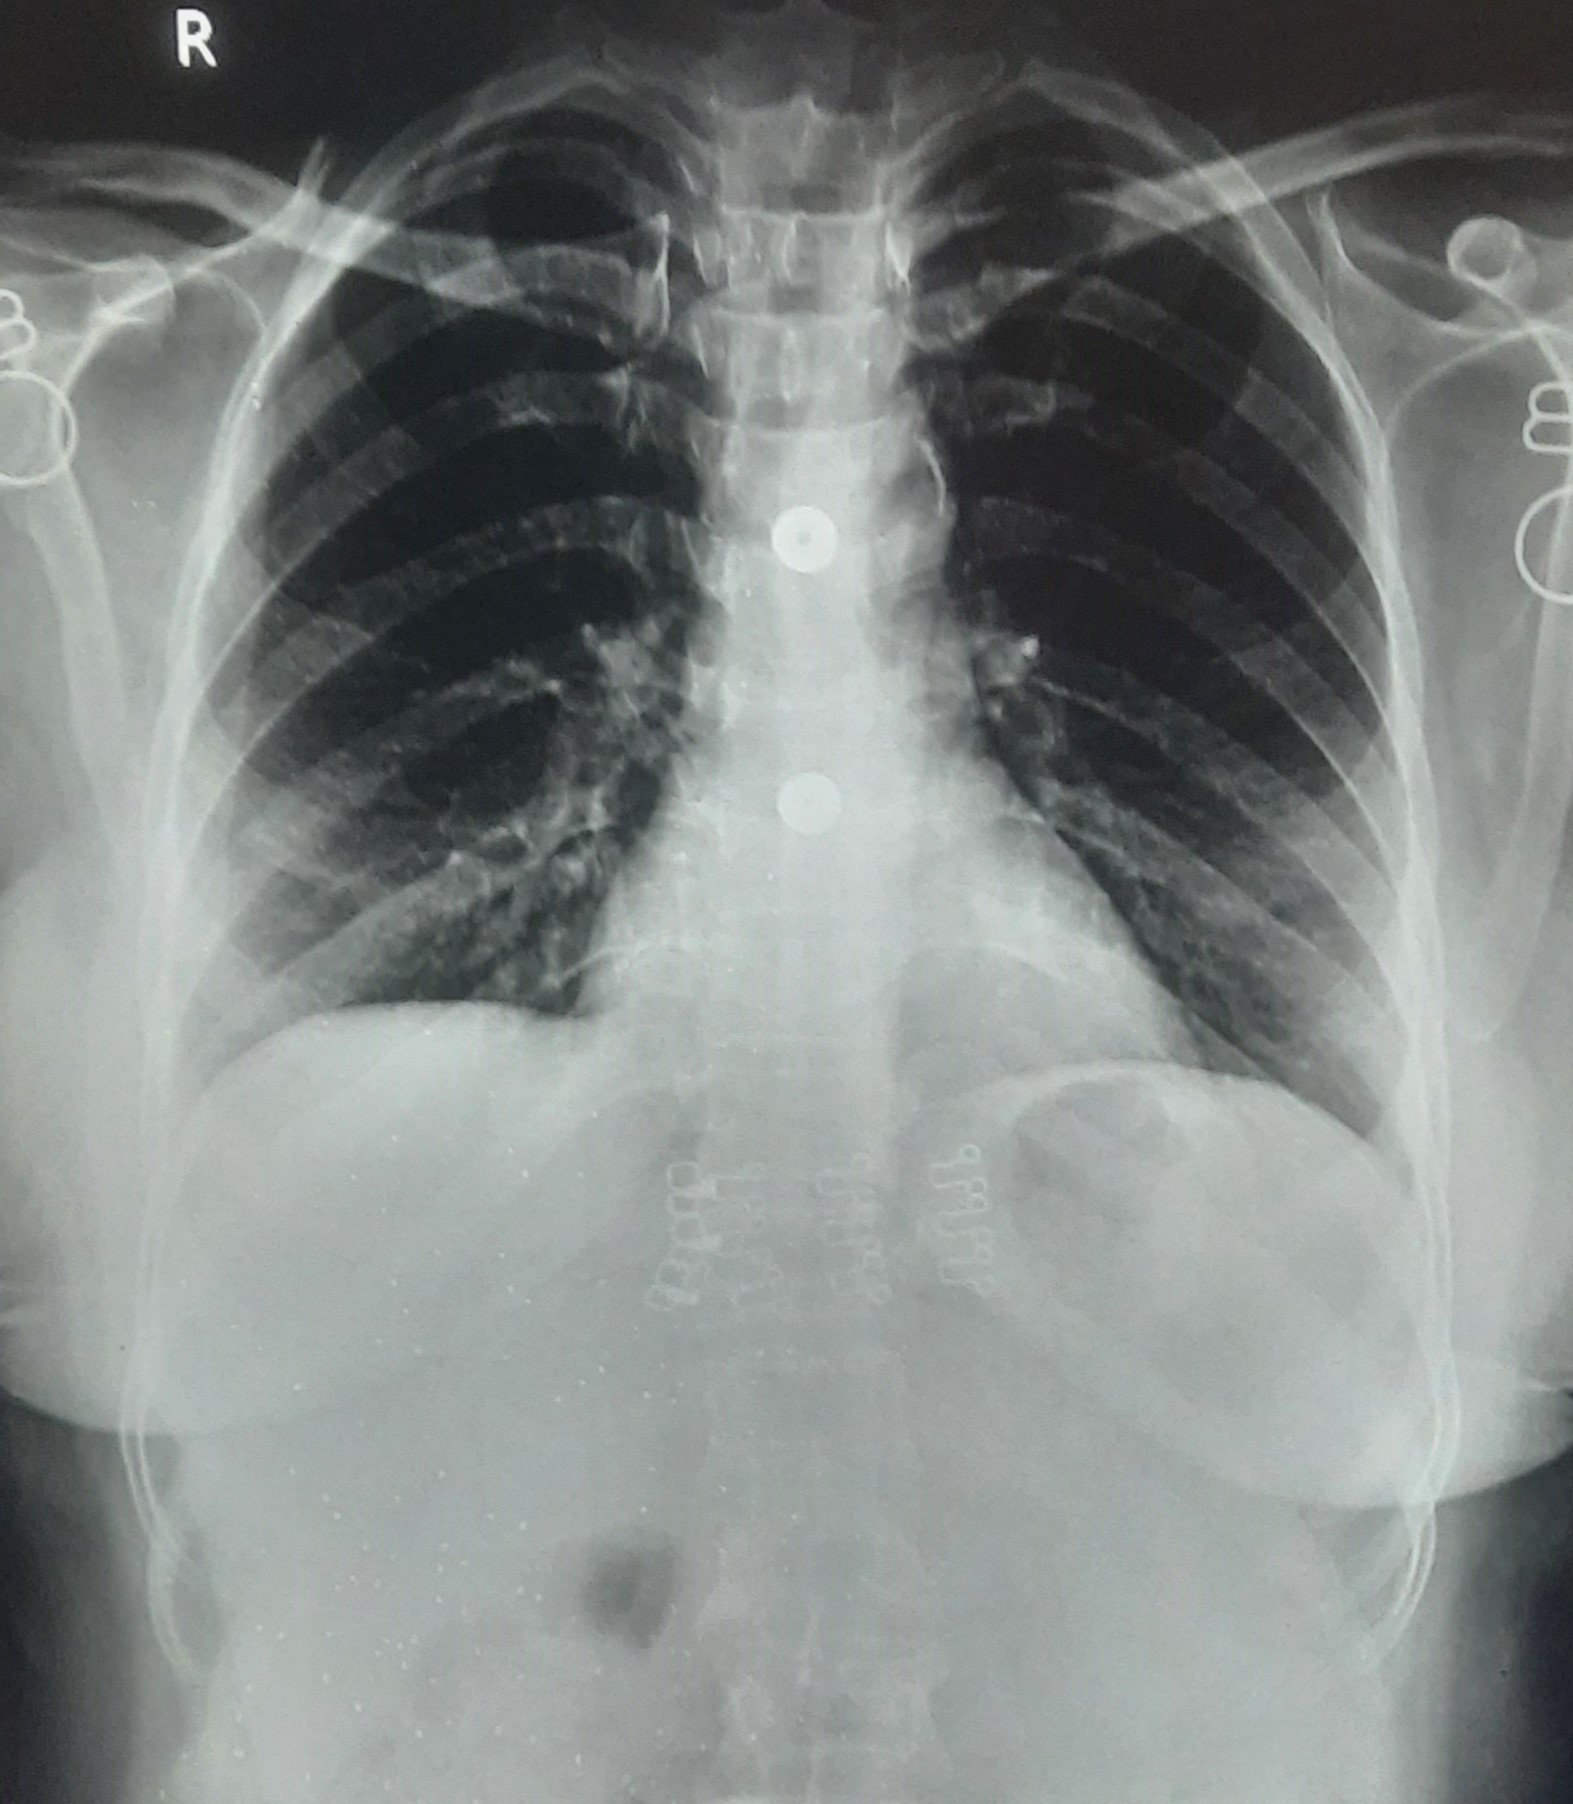

| 262 | IGGMC, Nagpur, Nagpur | P2 | 29-4210 | Mohamad Aslam | Consent taken on Paper | 35 Yrs. |

Provisional Diag : C/O Extra Pulmonary TB

Final Diag : FIBROSIS |

TB Case (Confirmed) | S/O RETICULAR OPACITIES NOTED IN RIGHT UPPER & MIDDLE ZONE/ QUERY FIBROSIS | Abnormality visible on x-ray |